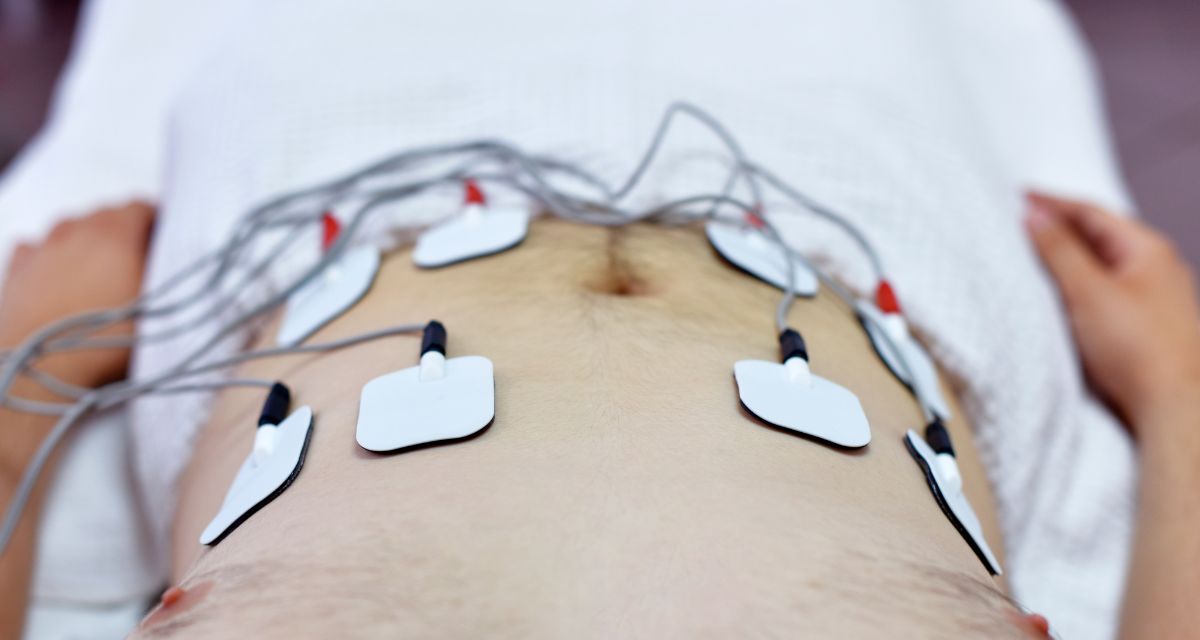

続いて3番の部屋に入ると、今まで受けたことのない心電図の検査でした。

上半身を脱いでベッドに横たわり、電極のニップを付けて心臓の筋肉に流れる電流を体表面から記録する検査ということです。初めてで少し不安でしたが検査自体は痛いとかもなく、これも無事に終了しました。